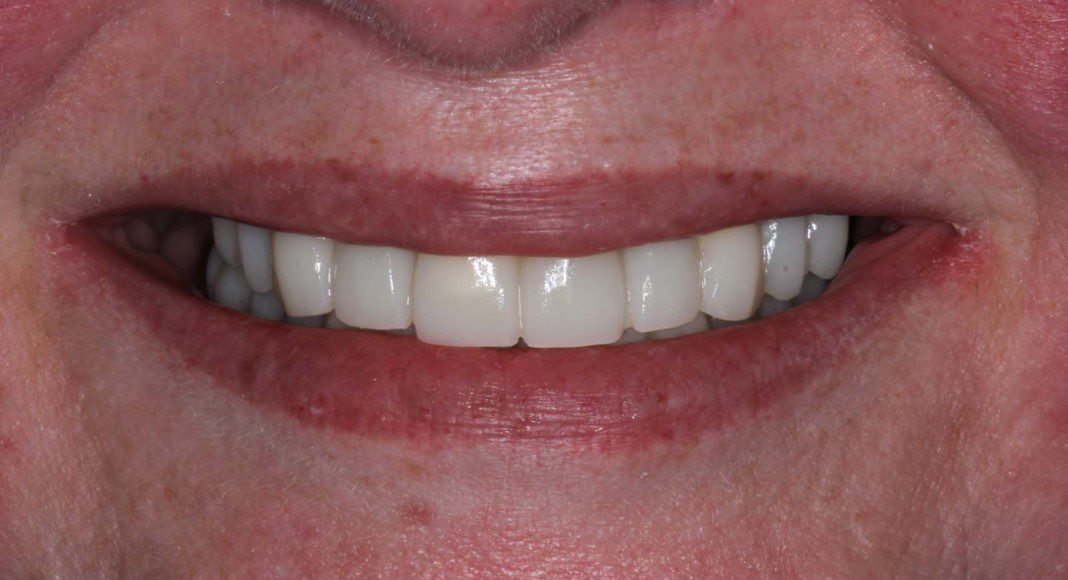

Occlusal view of the upper arch. Note: The tissues are a little red. Many patients, especially women have a slight allergy to the acrylic of the temporary bridges. This resolves after the zirconia bridge is placed.

Occlusal view, upper, day of delivery. If you look closely, you can see the final prosthetic screw (blue). This channel is covered with composite resin.